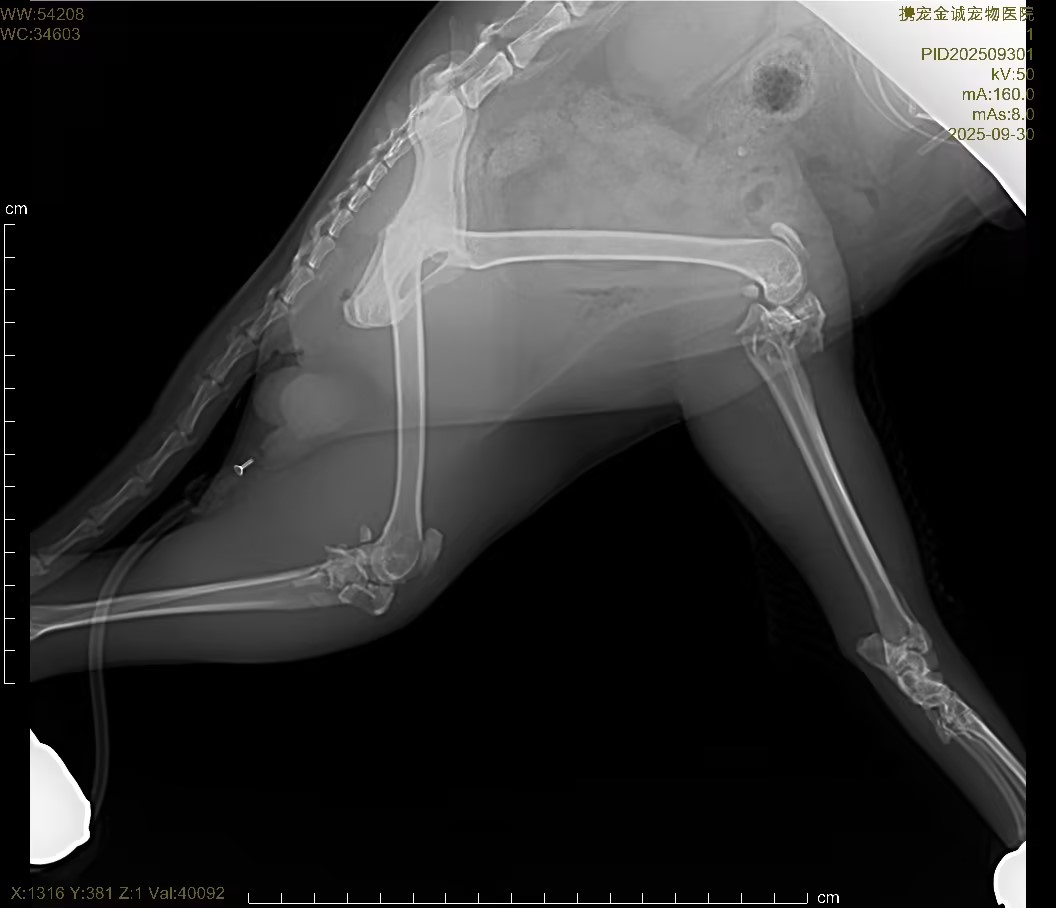

3.影像学检查(X 光)

对患猫胸腔、腹腔、全身骨骼进行数字化 DRX 光正侧位摄片,明确高空坠落所致骨骼、胸腔、腹腔脏器损伤情况:

骨骼系统

脊柱、四肢长骨可见骨连续性中断、骨皮质错位,确诊高空坠落所致外伤性骨折,骨折端无明显粉碎性重度破坏,适合微创固定修复;

骨盆结构轻度移位,无骨盆环破裂、无脏器卡压,无开放性骨折表现;

关节腔结构清晰,无脱位、无关节腔内积液。

胸腔脏器

双肺纹理略增粗,无气胸、无血胸、无肺挫伤重度实变;

心影轮廓正常,无胸腔积液、无纵隔移位,无致命性胸腔损伤。

腹腔脏器

腹腔内脏器位置正常,无游离气体、无腹腔积液,排除胃肠道穿孔、膀胱破裂等急腹症;

肝、肾轮廓未见明显破裂、移位,无急腹症影像学征象。

X 光结论:确诊四肢 / 躯干外伤性骨折,无气胸、血胸、腹腔破裂等致命性继发损伤,为骨 02 胶水微创骨折固定手术提供明确影像学依据,手术指征明确、安全性可评估。